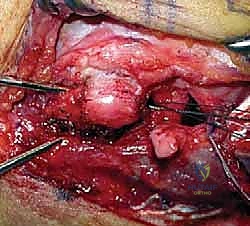

التدخل الجراحي: المعيار الذهبي

بالنسبة للغالبية العظمى من المرضى النشطين، والشباب، والرياضيين، تعتبر الجراحة هي الحل الجذري والوحيد لاستعادة استقرار الكوع ومنع التآكل الغضروفي المبكر (الخشونة). نظراً لأن الأربطة الممزقة بشكل مزمن تضمر وتفقد جودتها، فإن مجرد خياطتها (الإصلاح المباشر) غالباً ما يبوء بالفشل. لذلك، فإن الإجراء المفضل عالمياً والذي يبرع فيه الأستاذ الدكتور محمد هطيف هو إعادة بناء الرباط (Reconstruction) باستخدام رقعة وترية.